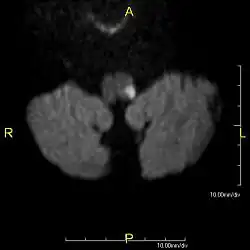

Clinical B1000 diffusion weighted MRI image showing an acute left sided dorsal lateral medullary infarct